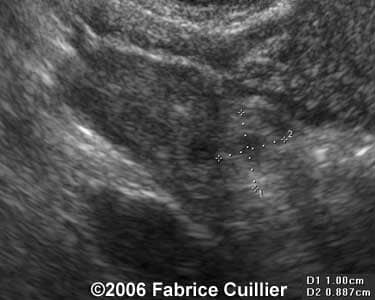

Case 4

case4a

case4b